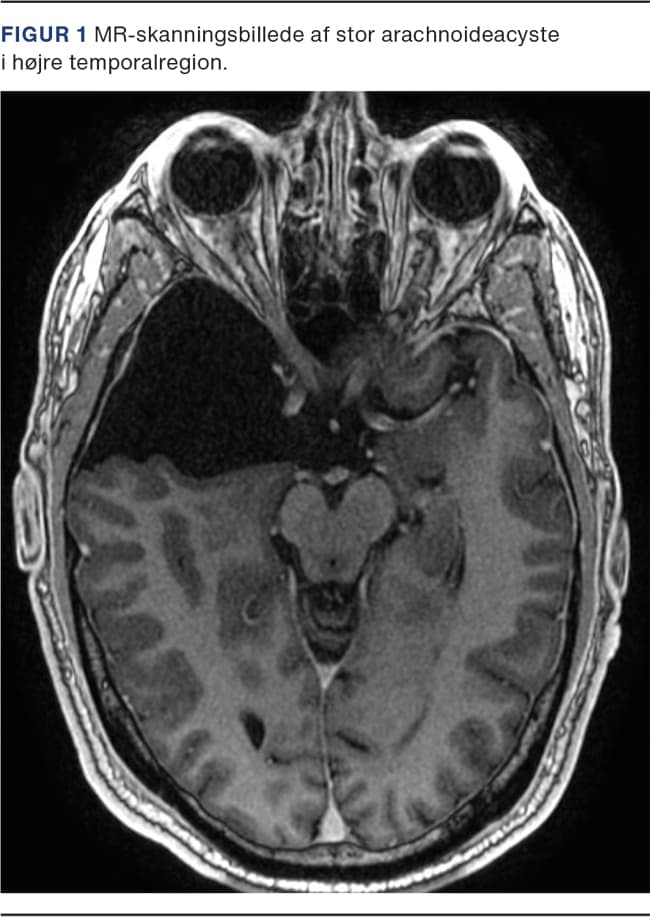

Arachnoideacyster (Figur 1 og Figur 2) er hyppige tilfældige fund på hjerneskanninger med en prævalens på 2% i befolkningen [1]. De betragtes som kongenitte strukturer, som udgår fra arachnoidea mater, den midterste hjernehinde, og indeholder cerebrospinalvæske. De kan opstå overalt, hvor der findes arachnoidea, inklusive i spinalkanalen. De intrakranielle arachnoideacyster ses oftest i fossa cranii media (55%), hvor de typisk er placeret mellem cerebrum og kraniet [1]. De findes her lidt hyppigere i venstre end i højre hemisfære, og blandt patienterne ses en lille overvægt af mænd [2].

MR-skanningsbillede af stor arachnoideacyste i venstre temporal­region.